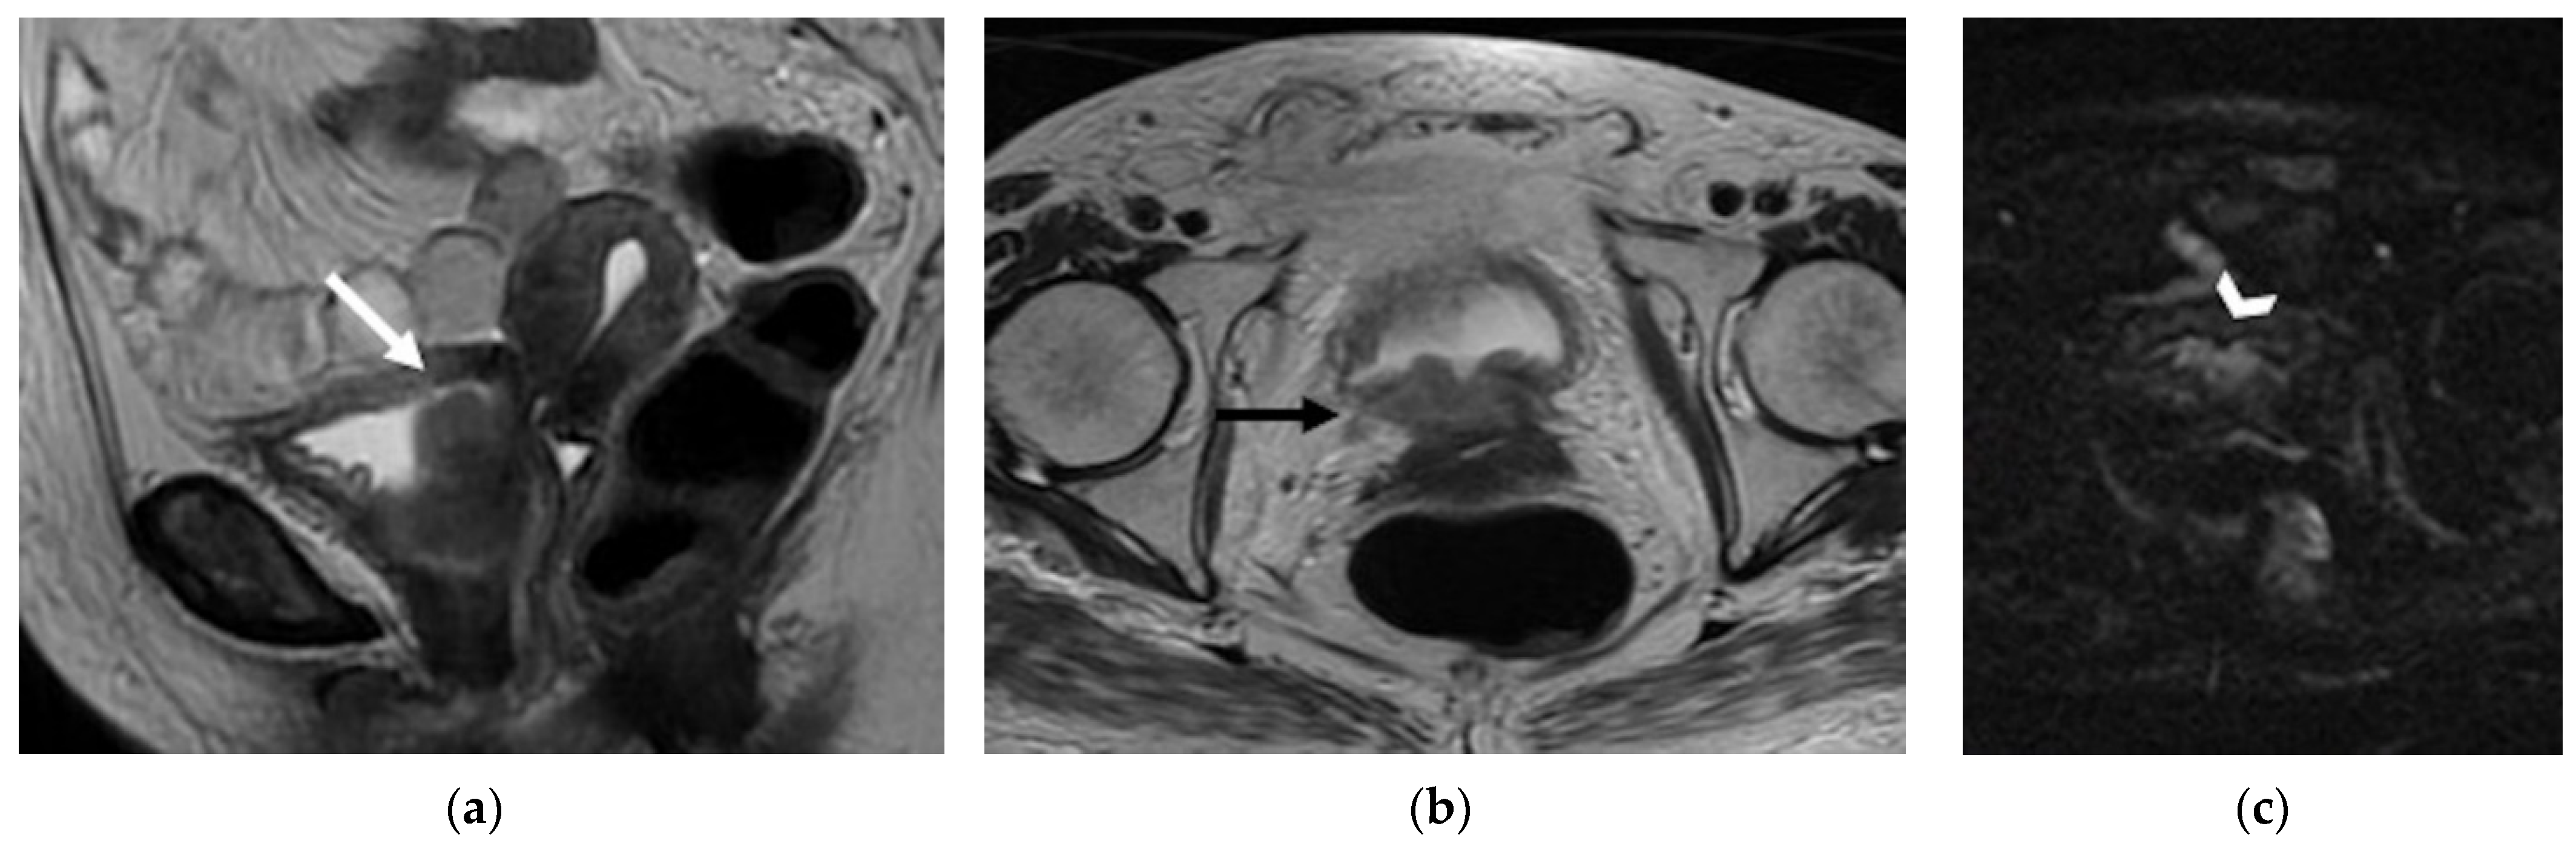

| Regional | |

| Anterior Urinary bladder and urethra ![]() |

|

| Posterior Rectal or sigmoid colon ![]() | An infiltrating, spiculated mass, causing rectal or sigmoid luminal narrowing.